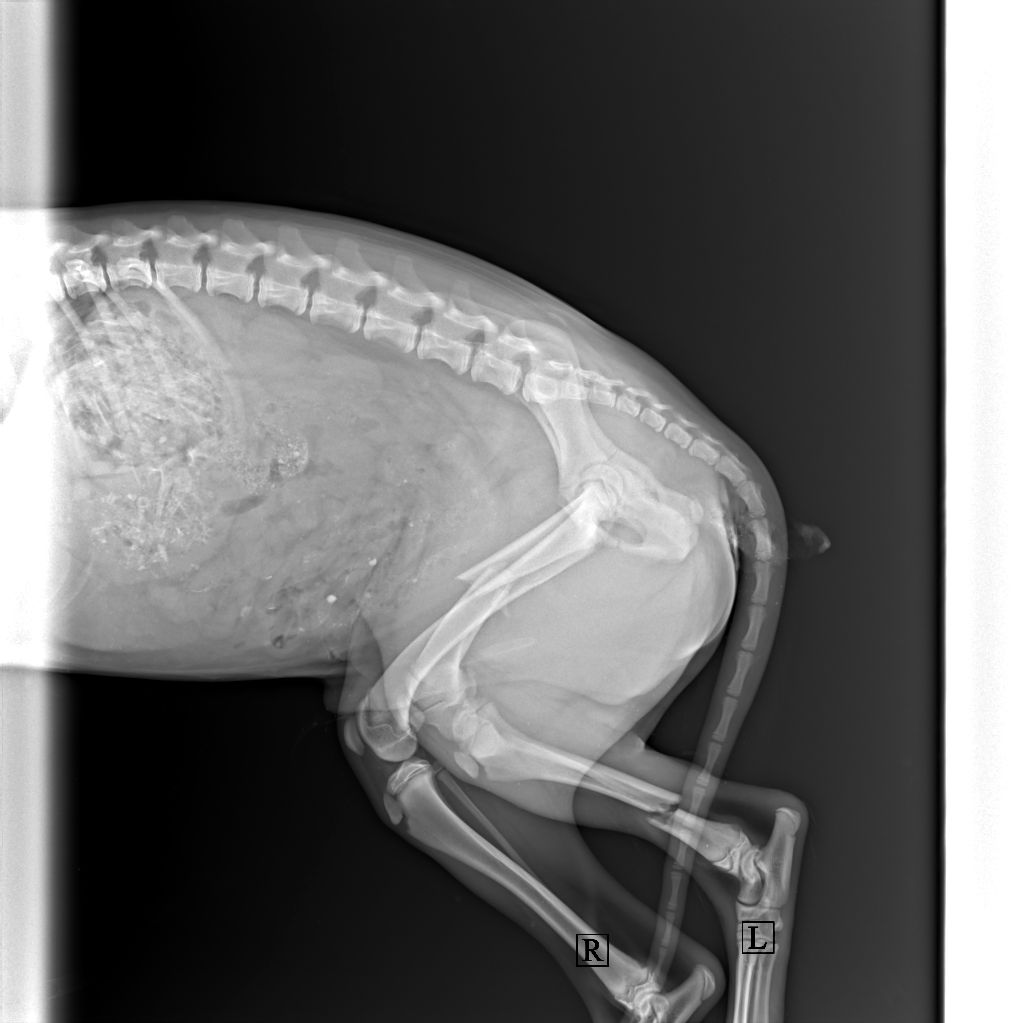

В ветеринарной клинике собаку осмотрели, сделали рентген и врач сообщил сразу о трех серьезных переломах.

Из заключения: "Перелом голени левой тазовой конечности, бедренной кости левой тазовой конечности, плеча левой грудной конечности".